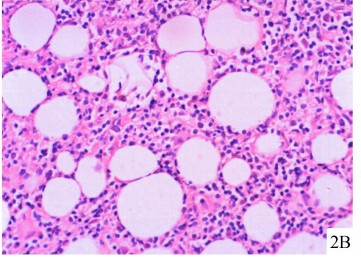

实验室检查大部分LEP患者ANA阴性,单独ANA阳性不能诊断为LEP。其病理学检查由脂肪细胞的透明性坏死,粉染物质的沉积。狼疮带试验通常在基底膜带发现免疫沉积物。